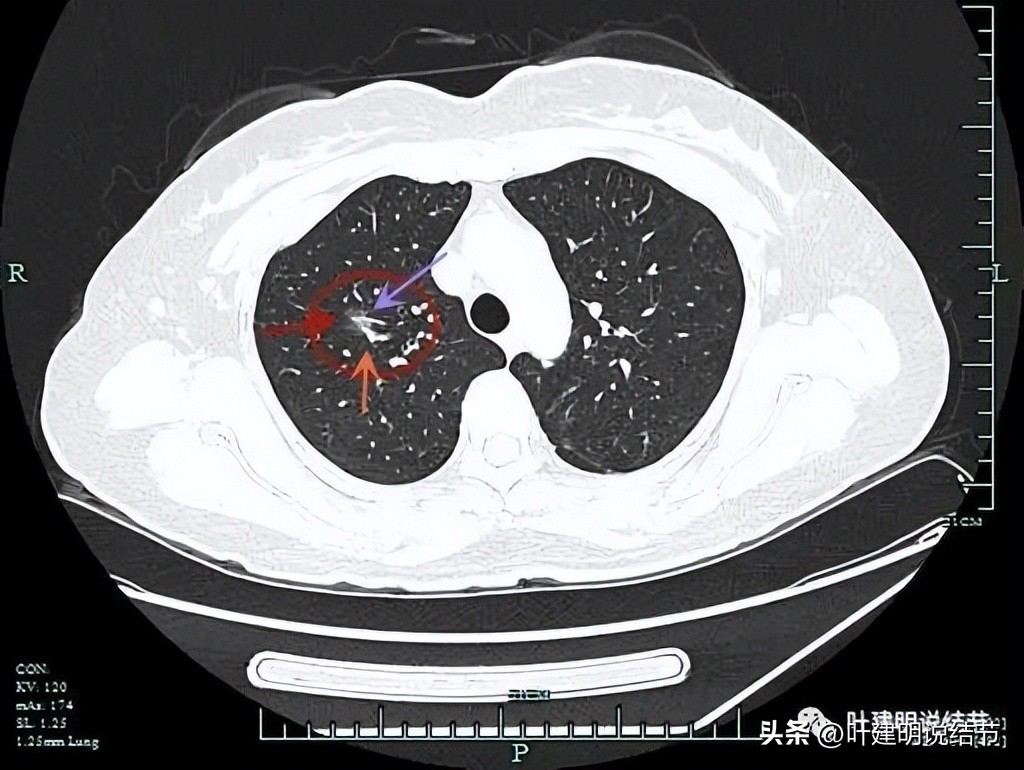

病灶出现,磨玻璃密度,瘤肺边界清,靠纵隔侧有少许实性成分。

实性成分明显,血管异常增粗,磨玻璃部分轮廓与界限清。

紫色箭头示细毛刺征,灶内血管穿行并有异常增粗。

明显的血管穿行与灶内血管增粗。

轮廓较清。